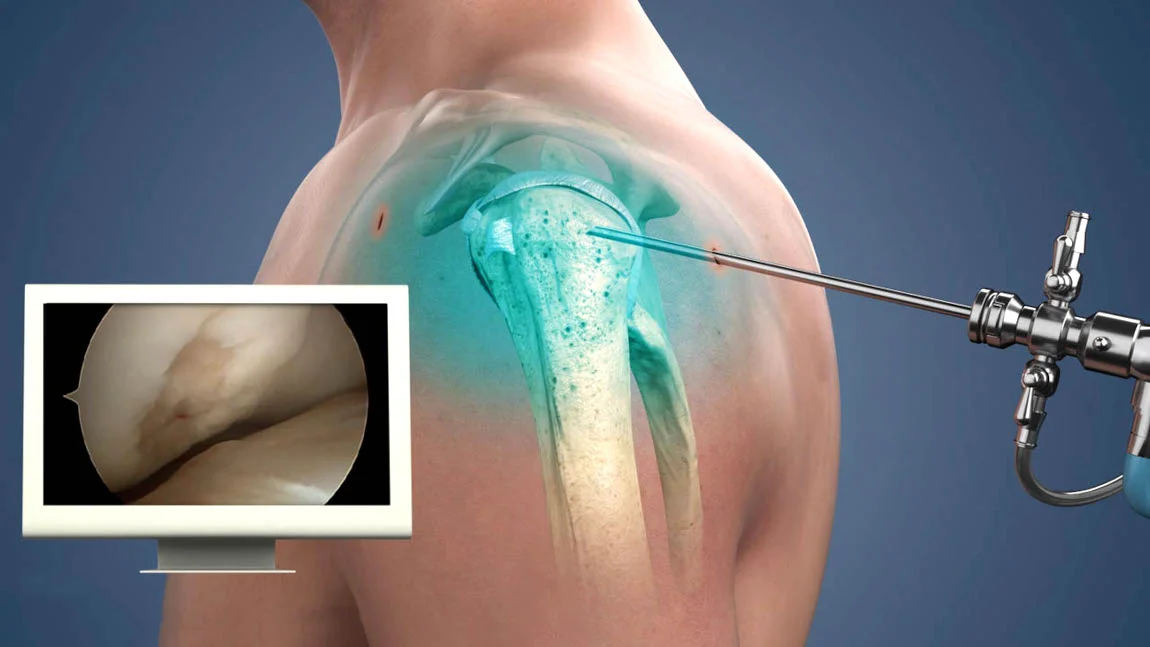

Arthroscopy Surgery

Arthroscopy surgery is a minimally invasive procedure used to diagnose and treat joint problems. A tiny camera called an arthroscope is inserted into the joint through a small incision, allowing the surgeon to see inside and perform necessary treatments with minimal damage.